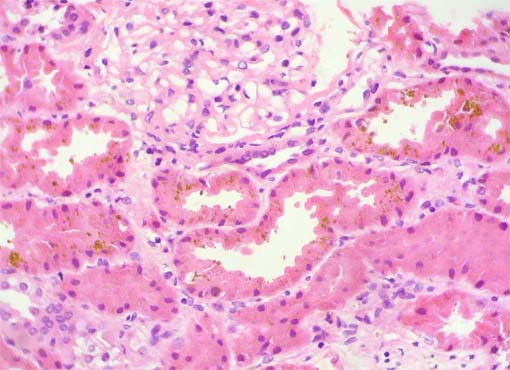

Figura 1.

H&E, X400.